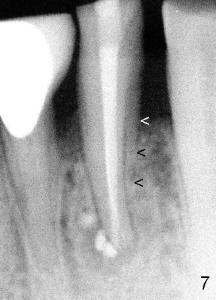

Sixty-two year old Chinese man presented to my office for new patient exam in June 2009. He has history of bruxism and wears night guard (Fig.1). The tooth #25 has incisal composite (*) with mild percussion. PAs show + PARL associated with #25 (Fig.2) and possible missing one canal (Fig.3; arrowheads point to possible 2nd root). RCT retreat was suggested. Extraction and implant were proposed as an alternative. In the next two 6-month appointments, he complained of mild pain in lower front tooth sometimes. RCT retreat was initiated on June 16, 2010. After removing composite, GP was removed with Chloroform and hand files. WL was determined by Root XZ at 15 mm. Debridement was done with hand files until #20 and rotary files until 30/.06 (Fig.4). The second canal was not found. It appears that some of GP was pushed outside of apical constriction (Fig.5 after Cavit). Twelve days later the patient returned to finish RCT retreat. It appears that symptoms improved after initiation of RCT retreat, although percussion is still mild. After removing Cavit and redebridement with #30 hand file, #10 precurved K file was inserted several times at different directions, hopefully getting into 2nd canal, which was not found. RCT filling was finished using AH Plus paste, master cone, lateral condensation with 1 medium fine accessory GP and vertical condensation (Fig.6). Composite build up was done immediately. Six months later, the patient insisted that pain is reduced substantially, but there is still mild percussion. PA shows persistent PARL (Fig.7 with outline with 2nd root (arrowheads)). Twelve months after RCT retreat, the patient is symptom-free, but objectively is not (including mild percussion and slightly enlarging PARL (Fig.8)). The 2nd canal is apparently lightly filled (red arrowhead).